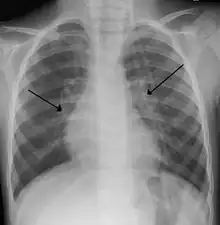

X-ray of a child with RSV bronchiolitis showing the typical bilateral perihilar fullness

Chest X-rays findings in children with RSV bronchiolitis are generally nonspecific and include perihilar markings, patchy hyperinflation, and atelectasis.[16] However, the American Academy of Pediatrics (AAP) does not recommend routine imaging for children with presumed RSV bronchiolitis because it does not change clinical outcomes and is associated with increased antibiotic use.[16][5] Chest X-ray is sometimes considered when the diagnosis of bronchiolitis is unclear or when there is an unexpected worsening.[5] In adults with RSV infection, chest films are often normal or demonstrate nonspecific changes consistent with viral pneumonia, such as patchy bilateral infiltrates.[36]